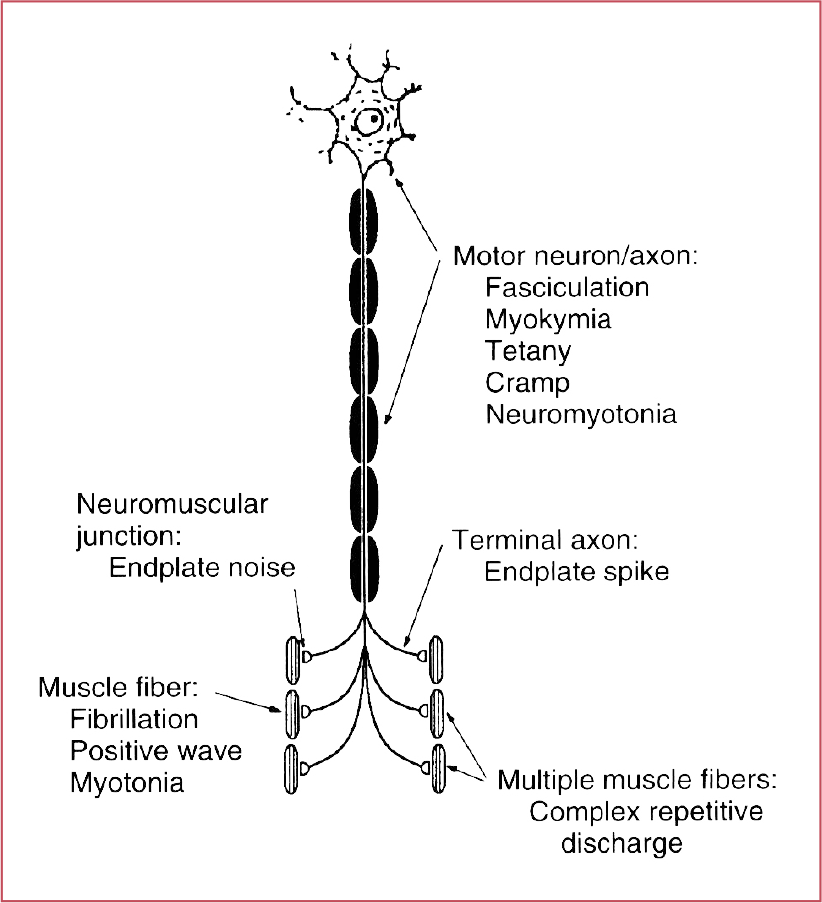

name two causes of myokymic discharges

radiation plexopathy, rattlesnake venom

On EMG, what types of abnormal sponteneous activity are generated by muscle fibers?

Myotonia, CRDs, FIBs, PSWs

What does an A- (Axon) Wave represent?

collateral sprouting following nerve damage